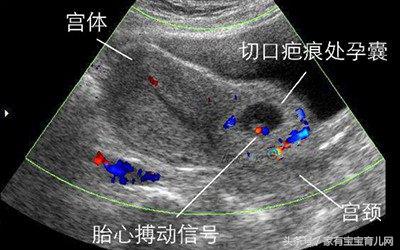

1、瘢痕子宫

子宫做过相关的手术是妊娠时候子宫破裂的较常见原因。如剖宫产、穿过或达到子宫内膜的肌瘤挖出术、输卵管间质部及宫角切除术、子宫形成术。妊娠晚期或临产后,由于子宫腔内压力增大,可使肌纤维拉长,发生断裂,造成子宫破裂。尤其术后瘢痕愈合不良者,更易发生子宫破裂。